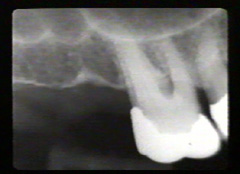

Las radiografías periapicales muestran pérdida de hueso alveolar en aproximadamente la mitad de la longitud de la raíz. La pérdida de hueso en el área de furacación se indica por la radiolucidez aumentada en la unión de las raíces en la región cervical.

En mesial del lateral derecho como en distal del central derecho aparece una perdida considerable de hueso. El puente fué realizado hace unos seis años como consecuencia de un accidente automovilístico.